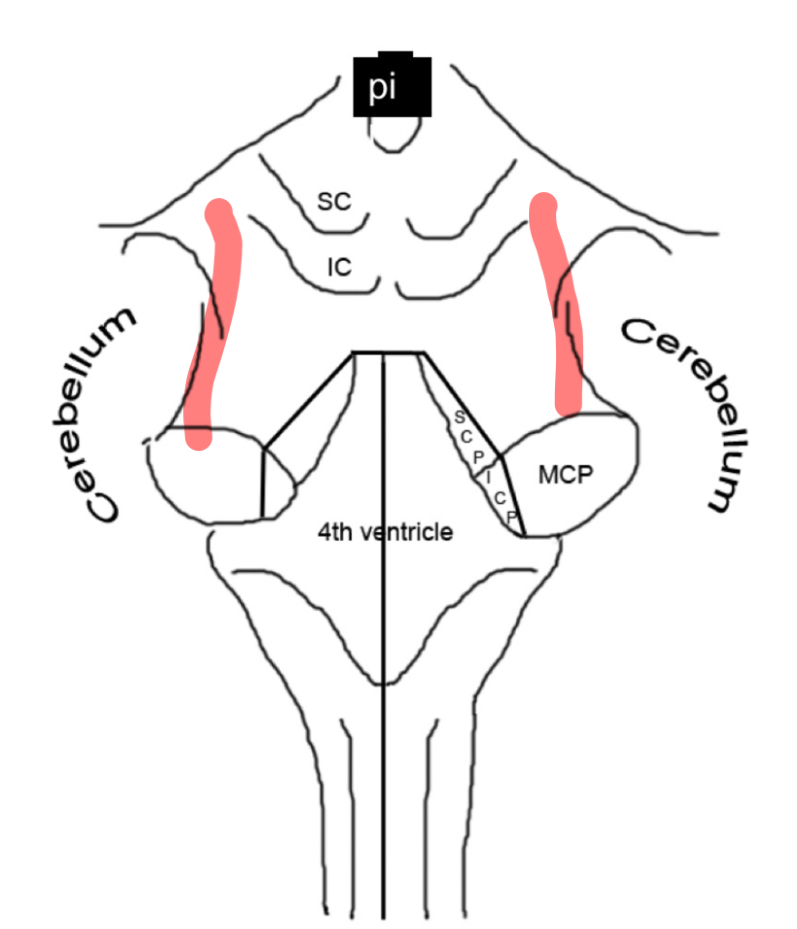

inferior cerebellar peduncle rostral medulla

middle cerebellar peduncle caudal pons

cerebellar peduncles

4th ventricle